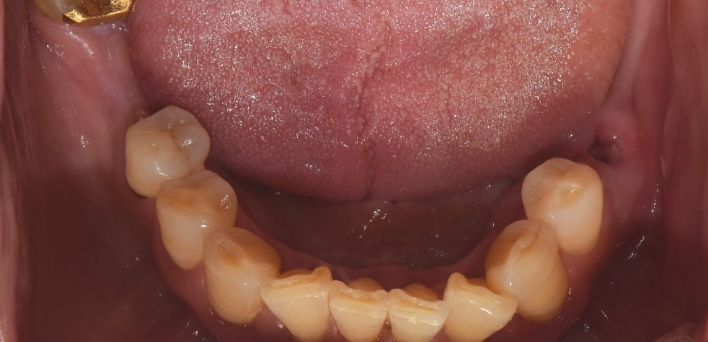

임플란트 : 손 ** 님 (50대)

치아가 있다는게, 아직도 정말 꿈만 같아요.

Before Before

2020.02.30

After After

※ 더서울치과의원은 의료법을 준수하며 위 케이스는 실제 환자의 동의를 얻은 사례로 치료 전, 후가 동일한 환경에서 촬영되었습니다.

환자 케이스에 따라 부작용이 발생할 수 있습니다. 이 부분은 의료진의 충분한 상담과 체크를 통해 예방하고 줄일 수 있습니다.

[임플란트 부작용] 수술 후 관리가 소홀할 경우 출혈, 주위염 등의 부작용이 발생할 수 있어 구강 위생을 철저히 유지하고, 정기적인 검진을 통해 상태를 점검하는 것이 중요합니다.

환자 특징

환자 특징01무치악 상태

환자 특징02수년간 무치악으로 지내심

임플란트가 불가능할것이라

생각하고 내원

위, 아래 6개씩 식립

디지털 풀아치 임플란트